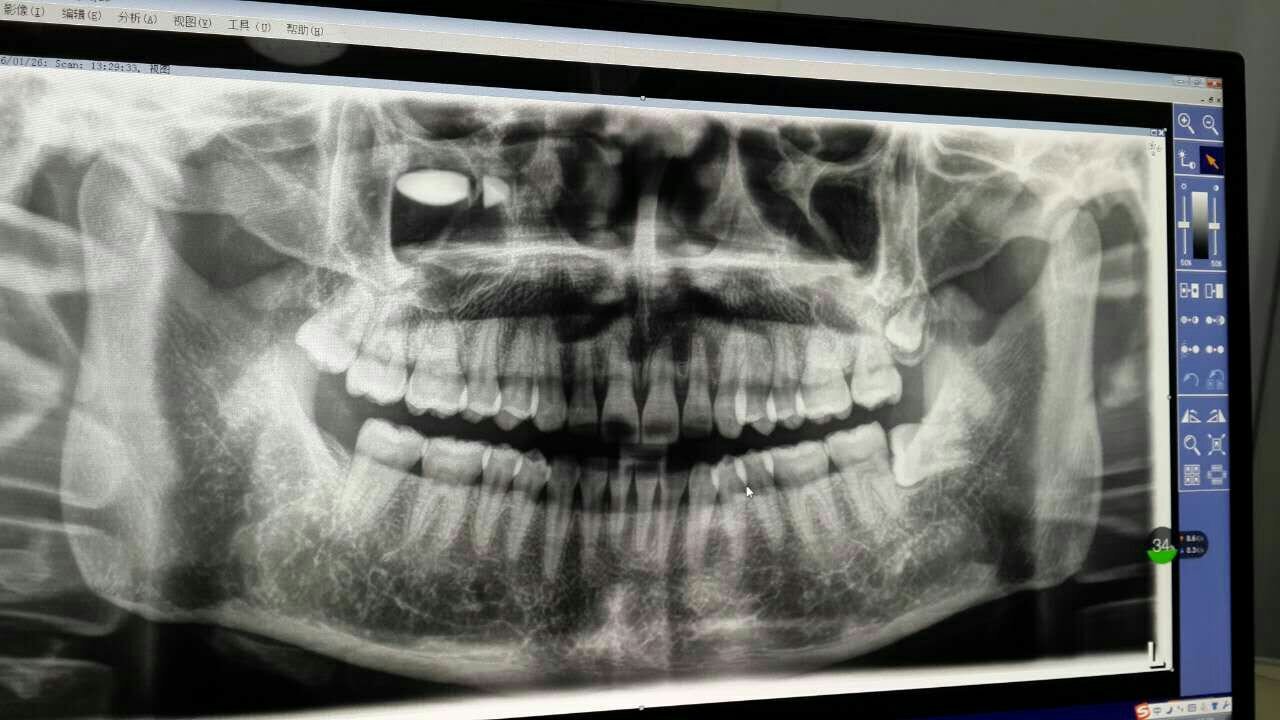

请教专业人士,我一次拔了三颗智齿,今天是第三天,前两天吃的布洛芬止疼片,一直打得消炎针,想要怀宝宝 请教专业人士,我一次拔了三颗智齿,今天是第三天,前两天吃的布洛芬止疼片,一直打得消炎针,想要怀宝宝得需要多长时间,还得注意些什么? 点击展开 匿名用户 2016-01-31 12:26 为您推荐: 其他回答 不要吃辣的。 匿名用户 2016-01-31 19:31 等牙齿好了吧 匿名用户 2016-01-31 12:28 相关问题 我刚拔完智齿,打麻药了没吃消炎药,过多久能要宝宝啊! 孕9周上火了,嗓子疼,智齿发炎,宝妈们有什么好方法消炎吗?求助! 哺乳期,智齿发炎,同侧牙龈和扁桃体,肿痛到食物和水都无法下咽,请问:用什么药物既可以消炎止痛,又不影响哺乳?谢谢~